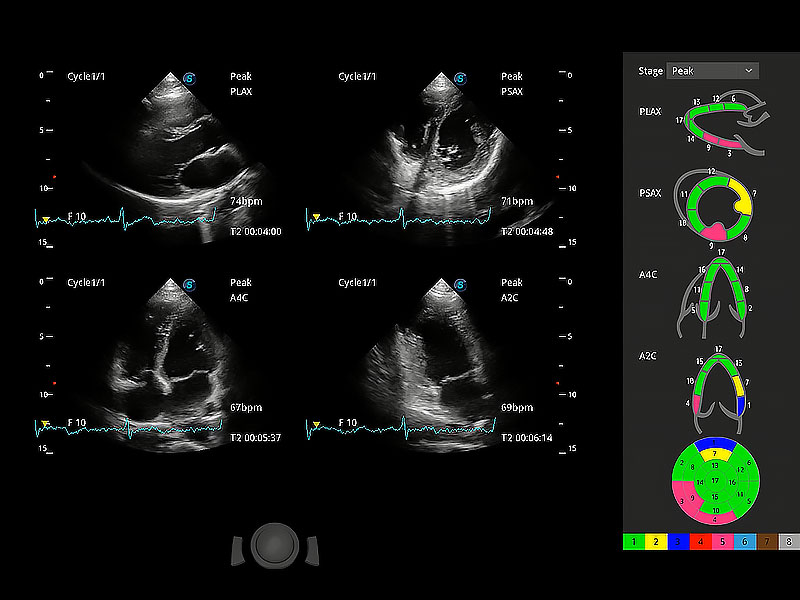

通過(guò)心肌識(shí)別技術(shù)與二維斑點(diǎn)追蹤技術(shù)相結(jié)合,對(duì)心臟的超聲圖像進(jìn)行量化分析。計(jì)算心肌17個(gè)節(jié)段的應(yīng)變、應(yīng)變率、速度、位移等,并通過(guò)牛眼圖的形式進(jìn)行呈現(xiàn)。